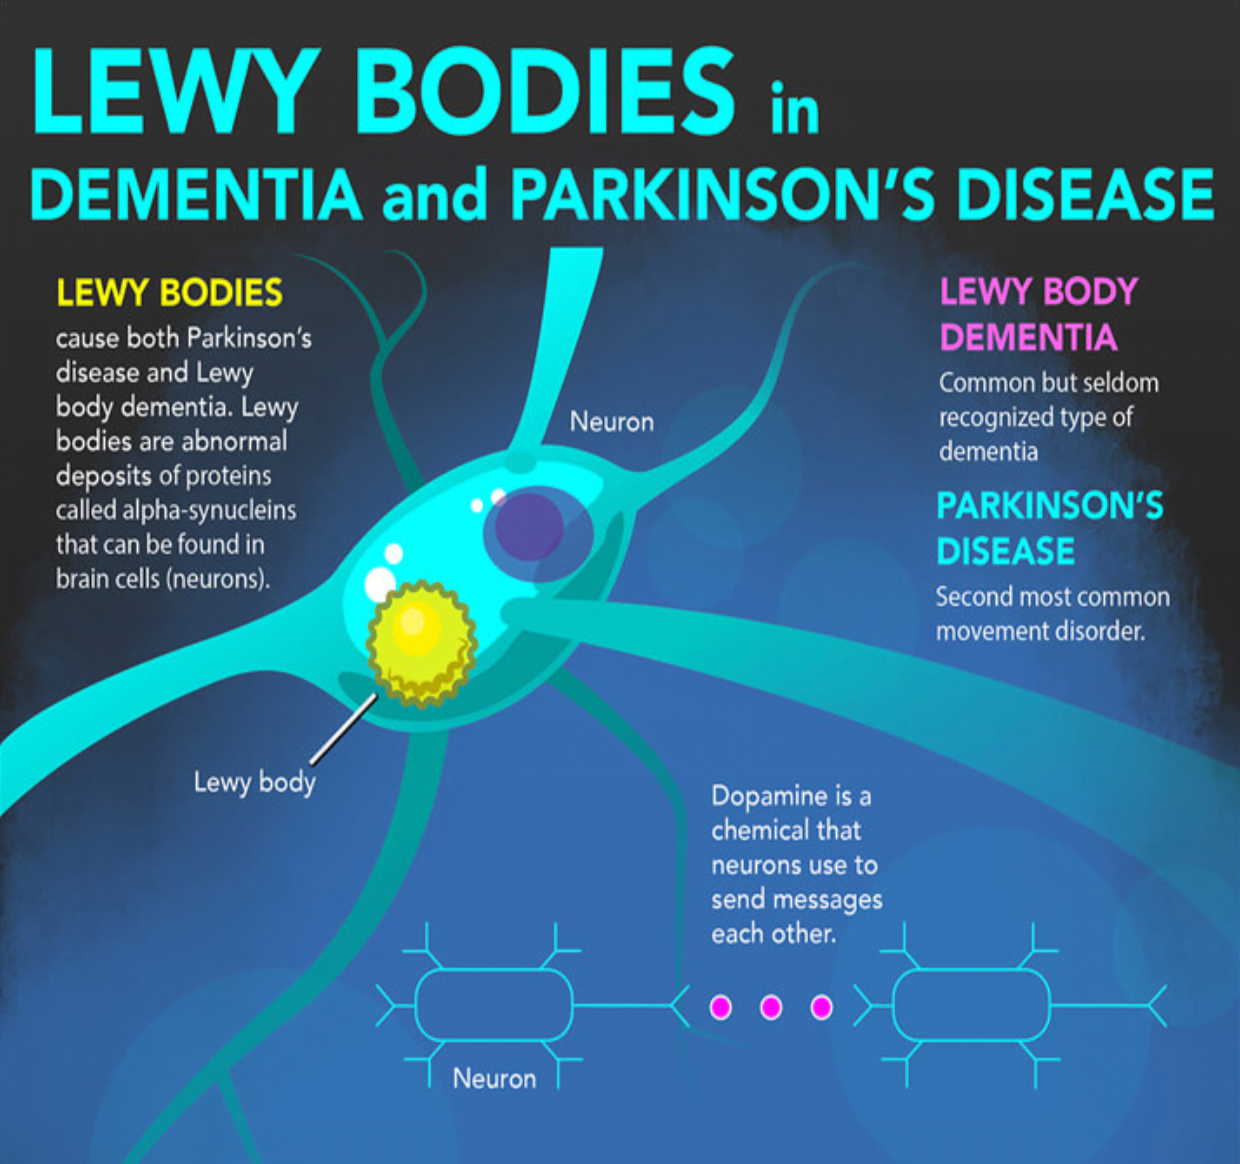

“Lewy Bodies in Dementia and Parkinson’s Disease” Infographic (NIH …

What is Lewy Body Dementia?? – The Ruby Pardue Blackburn Adult Day …